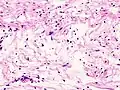

Micrograph of a schwannoma showing both a cellular Antoni A area (top) and a loose paucicellular Antoni B area (bottom). HE stain.

Verocay bodies are seen histologically in schwannomas.